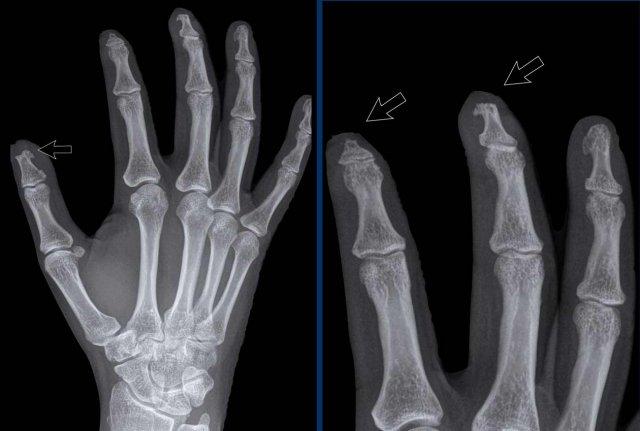

Ngón xúc xích

Hình ảnh điển hình của viêm ngón tay (dactylitis) “ngón xúc xích” với phù nề mô mềm và biến dạng bút chì trong cốc tại khớp liên đốt xa (DIP) 1-2 và 5 của bàn tay trái ở bệnh nhân viêm khớp vảy nến.

Lưu ý rằng các khớp bàn ngón tay (MCP) không bị tổn thương (khác với viêm khớp dạng thấp).

Viêm khớp vảy nến tiến triển

- Hình bên trái cho thấy bào mòn xương ở rìa khớp (mũi tên đen) và hình thành xương mờ nhạt (mũi tên xanh) tại khớp liên đốt ngón (IP).

- Về sau, bệnh tiến triển thành biến dạng bút chì trong cốc điển hình.

Phân bố tổn thương và sự hình thành xương khiến chẩn đoán viêm khớp dạng thấp ít có khả năng.

Các bào mòn xương ở rìa khớp và sự vắng mặt của tổn thương khớp liên đốt xa (DIP) ở các khớp khác khiến chẩn đoán viêm xương khớp bào mòn ít có khả năng, mặc dù biến dạng bút chì trong cốc có thể trông giống biến dạng cánh hải âu trong viêm xương khớp bào mòn.

Biến dạng bút chì trong cốc

A. Biến dạng bút chì trong cốc tại ngón chân thứ 1 và thứ 5.

B. Tiêu xương đầu ngón (acro-osteolysis) với tiêu xương chỏm đốt ngón xa của ngón 2-4 và 5.

Có bào mòn xương tại khớp bàn ngón chân (MTP) 2 và 3.

Viêm màng xương trong viêm khớp vảy nến

Đây là bệnh nhân viêm khớp vảy nến.

Lưu ý hình ảnh viêm màng xương mờ nhạt tại đốt ngón xa của ngón 1 bên phải (đầu mũi tên).

Có các bào mòn xương nhỏ tại chỏm đốt ngón xa của ngón 2 và 3 bên trái (mũi tên trắng).